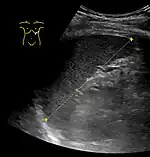

Spleen seen on abdominal ultrasonography

Maximum length of spleen on abdominal ultrasonography